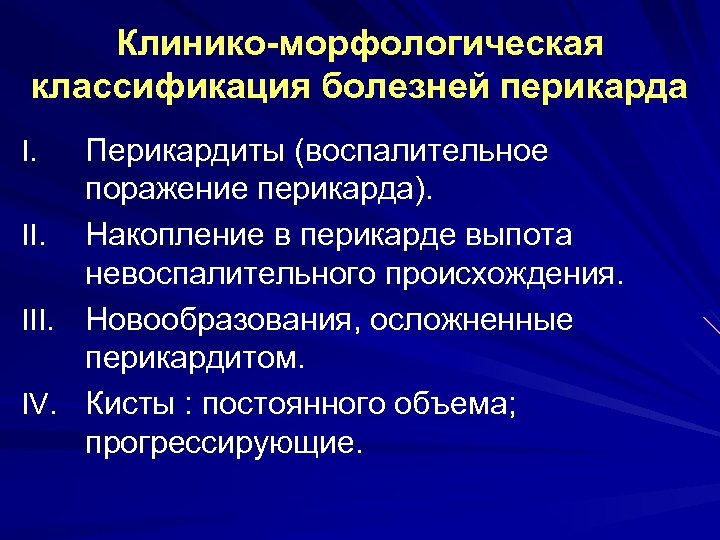

Клинико-морфологическая классификация болезней перикарда Перикардиты (воспалительное поражение перикарда). II. Накопление в перикарде выпота невоспалительного происхождения. III. Новообразования, осложненные перикардитом. IV. Кисты : постоянного объема; прогрессирующие. I.